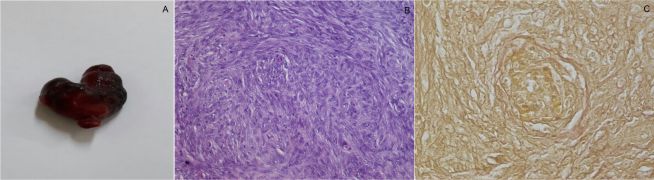

La masa pedunculada estaba compuesta por tejido conectivo muy vascularizado, con fibroblastos, fibrocitos y macrófagos, y tapizada por células epiteliales normales (Figura 3A-B). La masa nodular estaba compuesta por abundante cantidad de células fusiformes, dispuestas en bandas entrelazadas, con un núcleo único, grande, central, redondo u oval con un patrón de cromatina en grumos y moderada cantidad de citoplasma. No se observaron figuras mitóticas (Figura 4A-B). Mediante la coloración especial de van Gieson se confirmó la presencia de abundantes fibras de musculo liso y escaso tejido conjuntivo (Figura 4C). Se formuló el diagnóstico de pólipo y leiomioma uterinos. Se otorgó el alta médico y quirúrgico a los 10 días de la intervención. La paciente se recuperó totalmente. Doce meses post-intervención la misma concurrió a consulta para realizar un control anual en el cual se no se evidenciaron signos clínicos de la enfermedad.

(A). Masa uterina nodular: Leiomioma (B). Abundante cantidad de células fusiformes, dispuestas en bandas entrelazadas. Las células presentan un núcleo único, grande, central, redondo u oval con un patrón de cromatina en grumos y moderada cantidad de citoplasma. H&E. Barra = 50 µm. (C). Abundantes células musculares (amarillo) y escasas bandas de tejido conectivo (rojo). van Gieson. Barra = 50 µm.